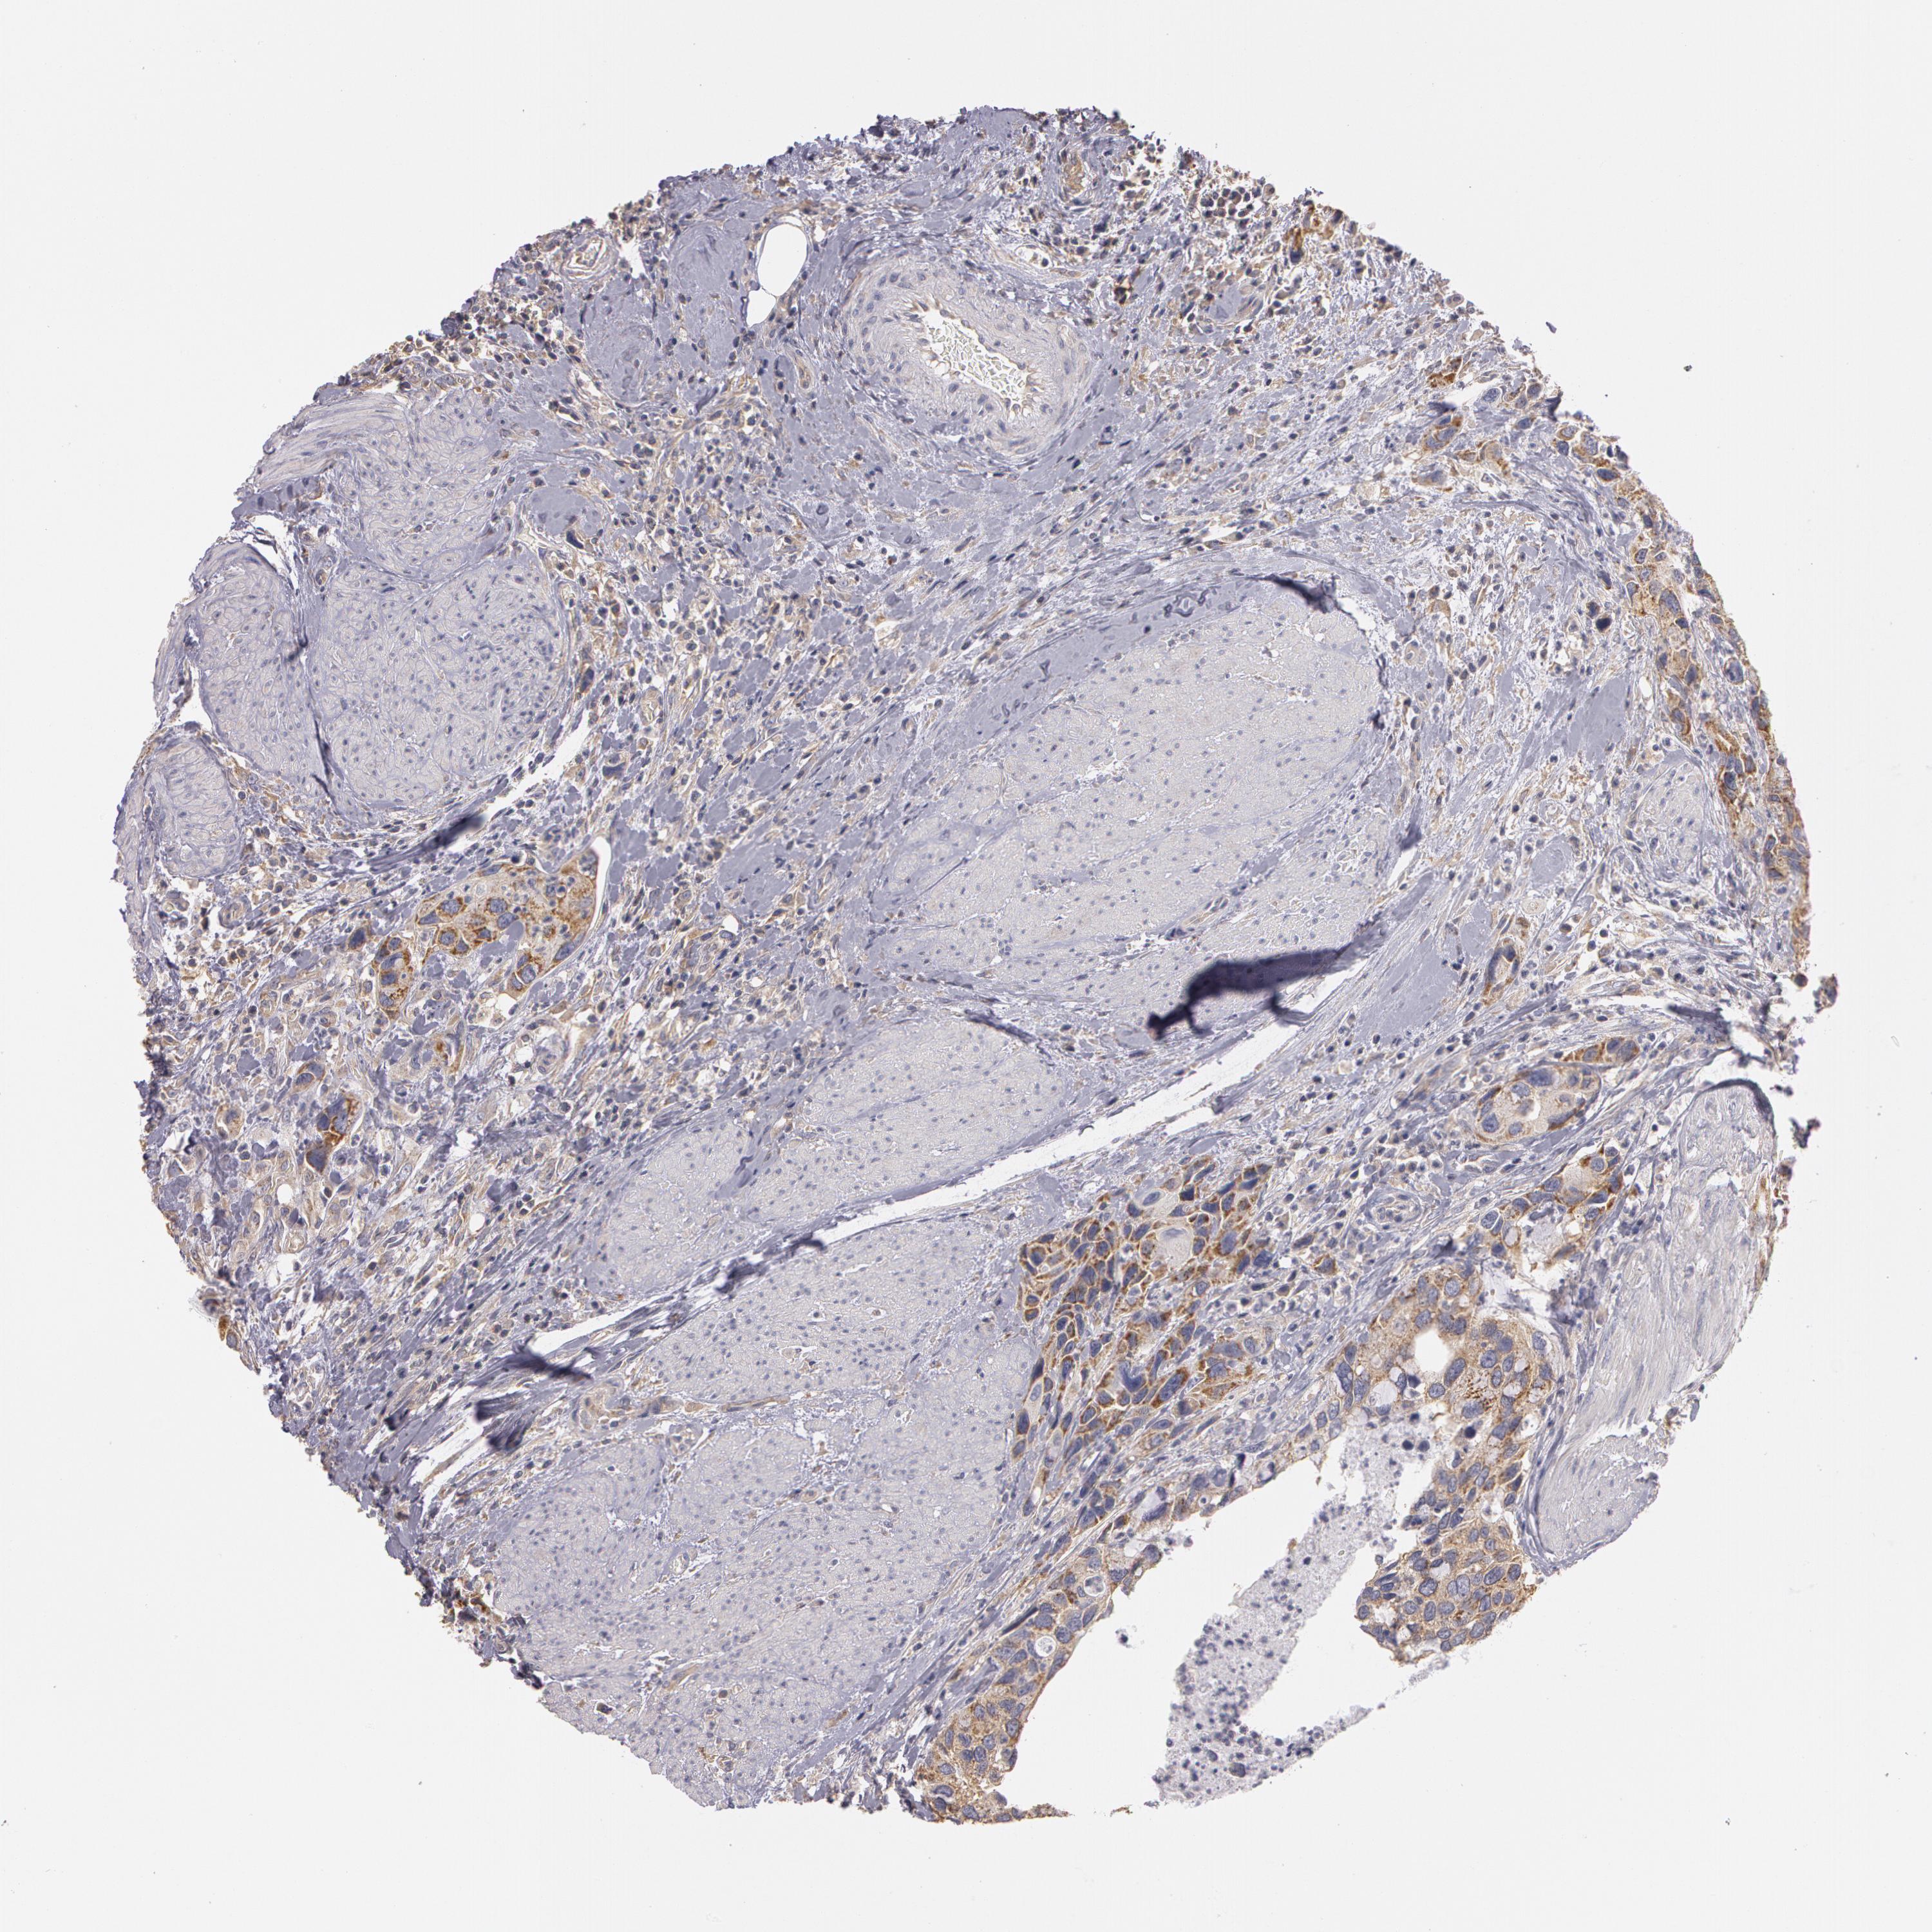

UROTHELIAL CANCER - Protein expressioni

A mouse-over function shows sample information and annotation data. Click on an image to view it in a full screen mode. Samples can be filtered based on level of antibody staining by selecting one or several of the following categories: high, medium, low and not detected. The assay and annotation is described here.

Note that samples used for immunohistochemistry by the Human Protein Atlas do not correspond to samples in the TCGA dataset.

Antibody stainingi

Antibody staining in the annotated cell types in the current human tissue is reported as not detected, low, medium, or high, based on conventional immunohistochemistry profiling in selected tissues. This score is based on the combination of the staining intensity and fraction of stained cells.

Each image is clickable and will lead to virtual microscopy that enables deeper exploration of all samples and also displays staining intensity scores, fraction scores and subcellular localization as well as patient and tissue information for each sample.

Antibody HPA001405

Staining

High

Medium

Low

Not detected

Intensity

Strong

Moderate

Weak

Negative

Quantity

>75%

75%-25%

<25%

None

Location

Nuclear

Cytoplasmic/membranous

Cytoplasmic/membranous,nuclear

Urothelial carcinoma, High grade

Urothelial carcinoma, Low grade

Adenocarcinoma, NOS